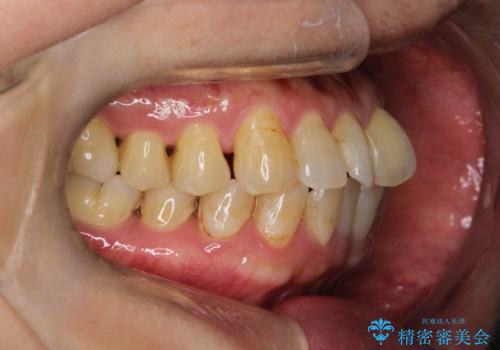

- 前歯のガタガタを主訴に来院されました。

上の歯の前突も気になってたため、奥歯の遠心移動も行いながらインビザラインにて治療を行いました。

今回は奥歯の遠心移動とIPRを行って配列しています。